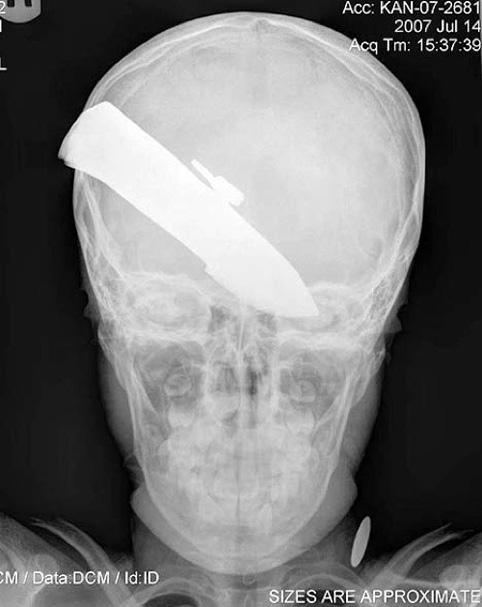

Толгойдоо 17 жил хутгатай явжээ

Сальвадорын нэгэн эмнэлэгт удаан хугацаатай үргэлжилсэн мэс заслын үеэр өвчтөний тархинаас 9 см урт хутганы ир гаргаж авсан байна. Гуталчнаар ажилладаг түүн рүү бүр 1995 онд хэсэг мансуурагчид халджээ. Тэд мэдээж гуталчны цавууг булааж авахаар дайрахад гуталчин эсэргүүцэж зодоон болсон байна. Энэ үедээ тэд толгой руу нь хутгалсан ч цус гараад л өнгөрсөн гэдэг. Тэгээд л эдгэрсэн, түүнээс хойш ер анзаарахгүй байсан ч сүүлдээ толгой нь хүчтэй өвдөх болсноос эмнэлэгт үзүүлж мэс засал хийлгэсэн нь энэ гэнэ.